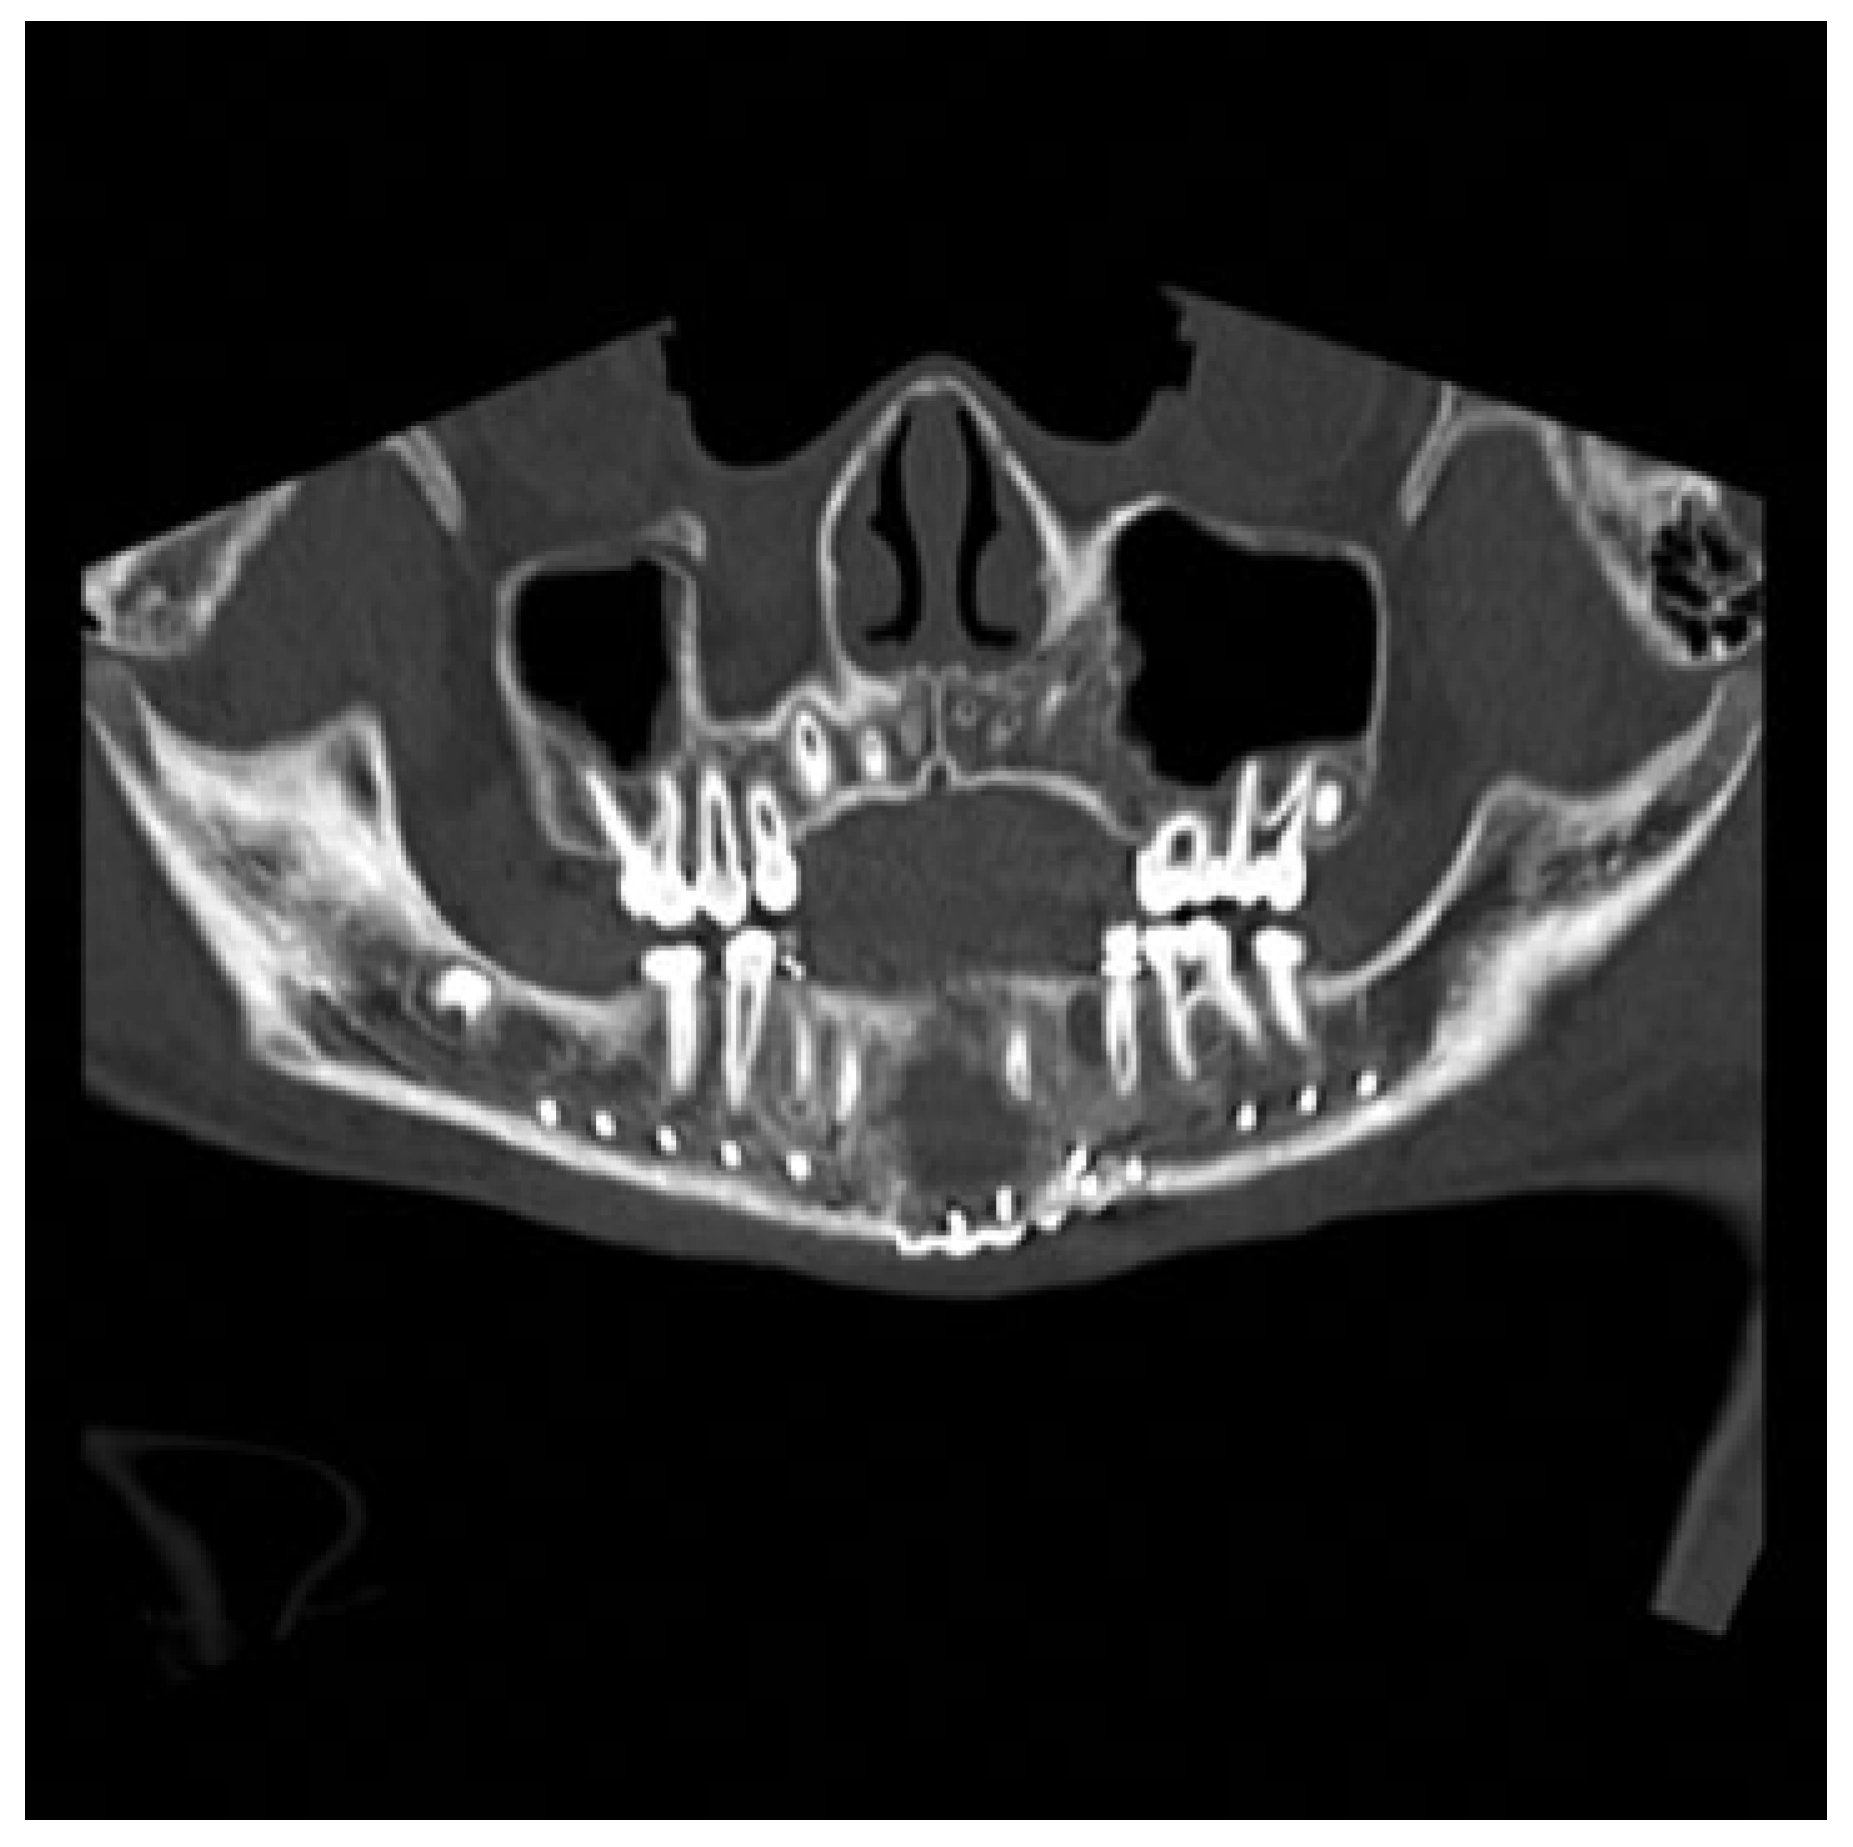

The Otolaryngology-Head and Neck Surgery department was consulted upon arrival to our ED. Physical examination revealed tenderness of the left side of the mandible and a visible intraoral step-off between the left mandibular lateral incisor and canine tooth. The CT was reviewed and demon- strated a significantly displaced fracture of the left para- symphysis. The fracture was deemed pathologic secondary to an apparent preexistent cystic lesion of the mandibular symphysis measuring 2.5 × 1.5 × 1.5 cm, with evidence of bony expansion (Figure 1).

Figure 1.

Coronal computed tomography (CT) scan revealing a parasymphyseal fracture in line with a cystic cavity.